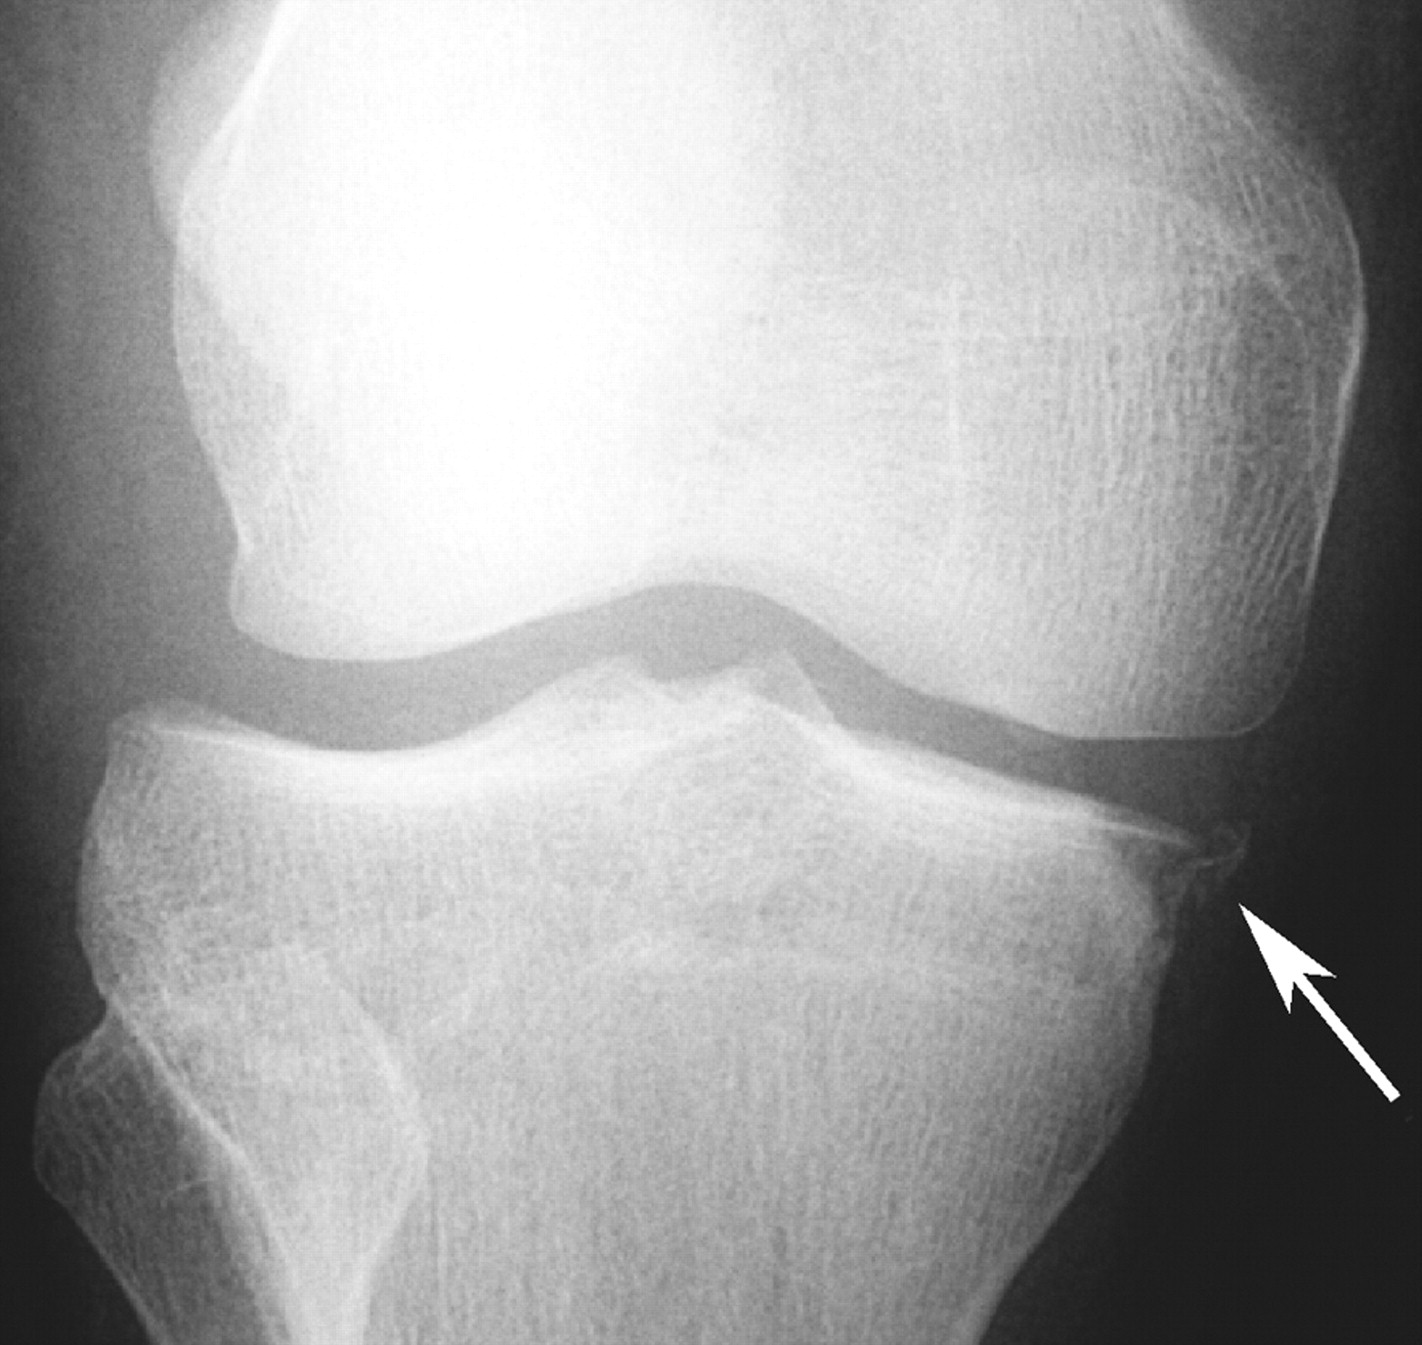

Segond Fracture

This is a very subtle "avulsion fracture of the tibia below the articular margin" caused by traction on the capsular or coronary ligaments. It is not possible to cause this fracture without first rupturing at least one of the major ligaments in the knee.

Examples in order of increasing subtlety: -